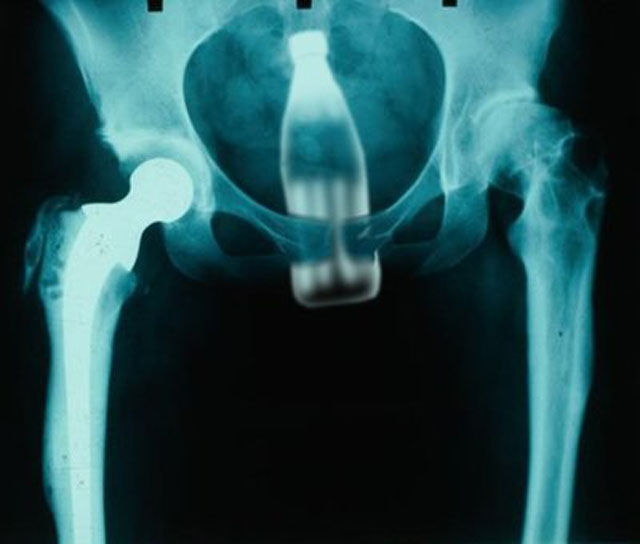

A new hip didn't slow this person down